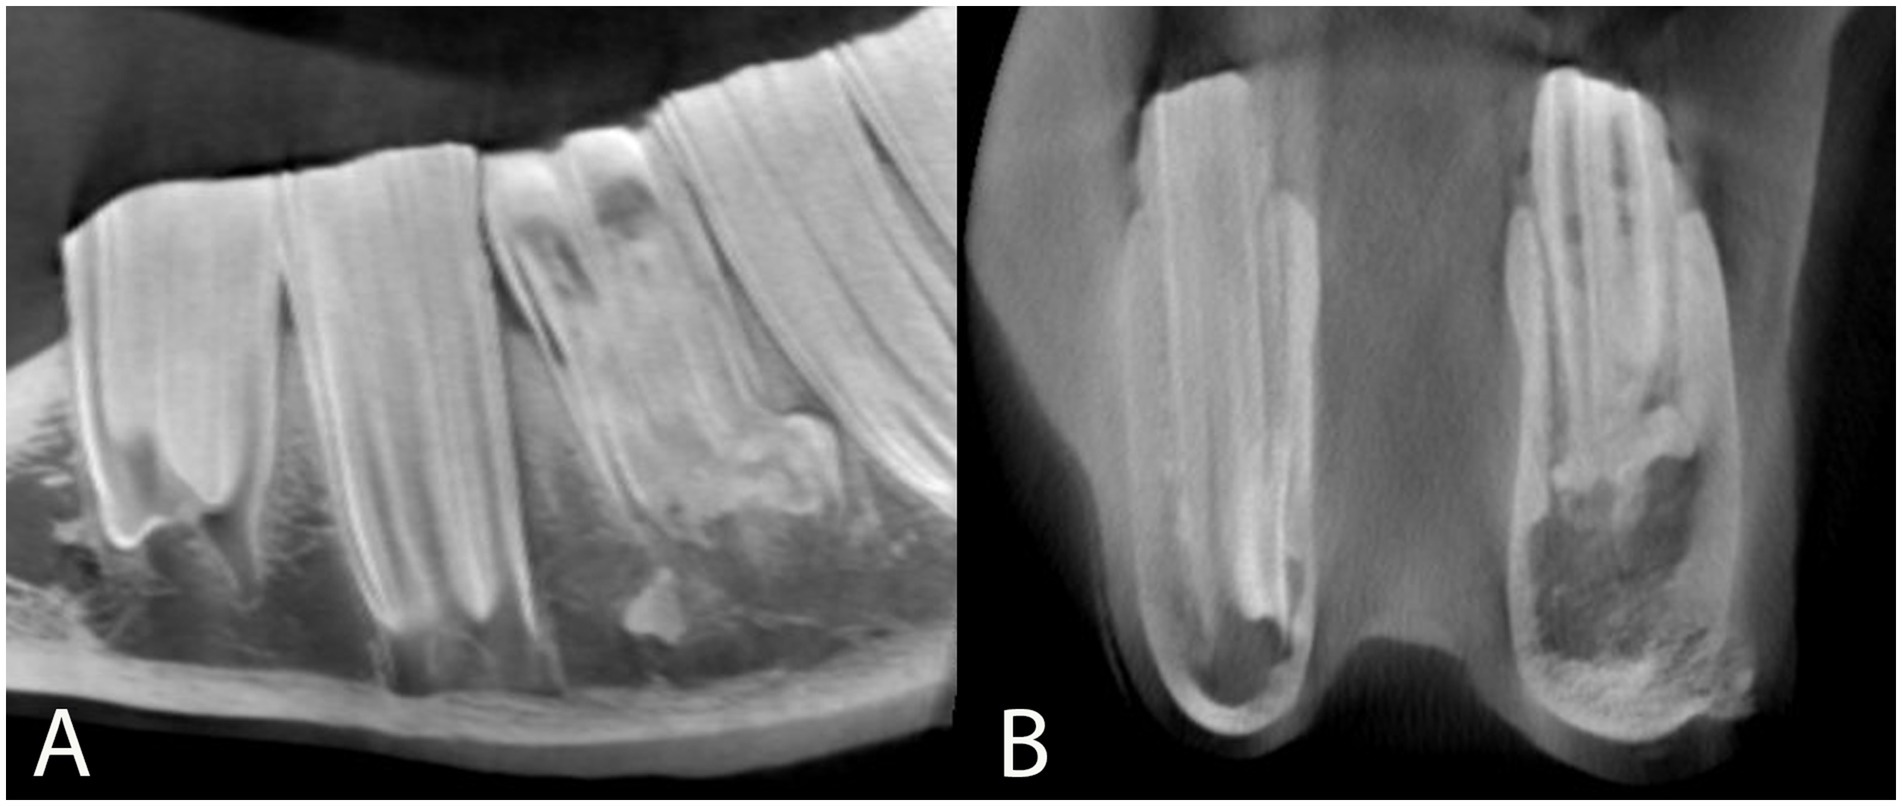

Apical malformation and enlargement (including peripheral cementum deposition) was found in five subjects to varying extents, all of whom had a mandibular cheek tooth affected (Table 1; Figure 8).

Figure 8. Sagittal (A) and transverse (B) multiplanar reconstructions of a preoperative cone beam computed tomographic scan through tooth 308 (case 7) also shown in Figure 3. The apical aspects of this tooth are malformed, showing a distal bulbous enlargement and a lingual and buccal bulbous widening on its mesial aspect. (A) Note the decreased coronal width of 308 at its occlusive surface and the mild horizontal alveolar bone loss mesial to 308. An isolated fractured root fragment is visible on the mesial aspect of the roots of tooth 308. Additional computed tomographic findings at the level of this tooth are diffuse endosteal thickening of the ventrolateral left mandibular cortex and mild adjacent soft tissue swelling. This cortex shows a focal cortical interruption as well as periosteal reaction. The mesial and distal infundibula of tooth 308 are hypoattenuating and widened, compatible with infundibular hypoplasia. (B) Note the close contact between the bone and the apical region of the affected tooth, while the periodontal space is widened apical to this malformation on the buccal aspect.